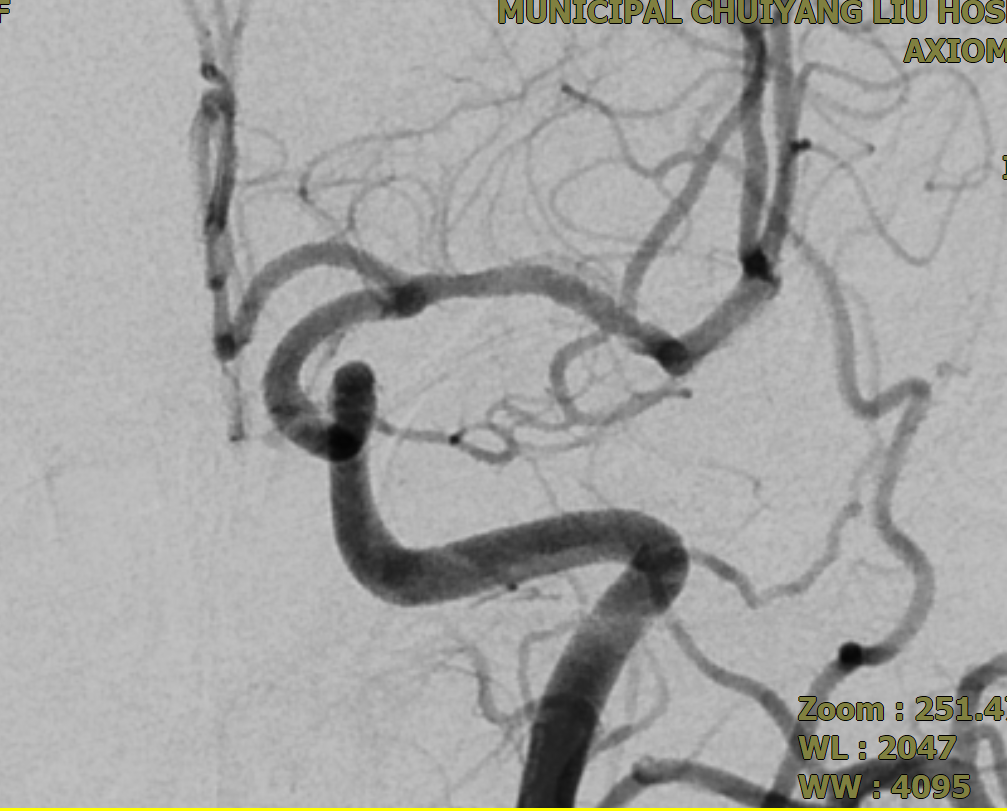

▲术后3个月复查DSA

为精准把握手术指征与安全,术前,需完善全脑血管造影对动脉瘤的形态、大小及载瘤动脉的血管条件进行全面评估;术中,需由经验丰富的神经介入医生精准将密网支架植入病变部位;术后,患者需严格遵医嘱服用抗血小板药物,以预防支架内血栓形成及缺血性卒中事件的发生,并需定期复查全脑血管造影,以评估动脉瘤的最终闭塞情况。本例患者行密网支架植入术后三个月复查全脑血管造影,结果显示密网支架贴壁良好,无支架内血栓形成,继续用药和定期复查即可。